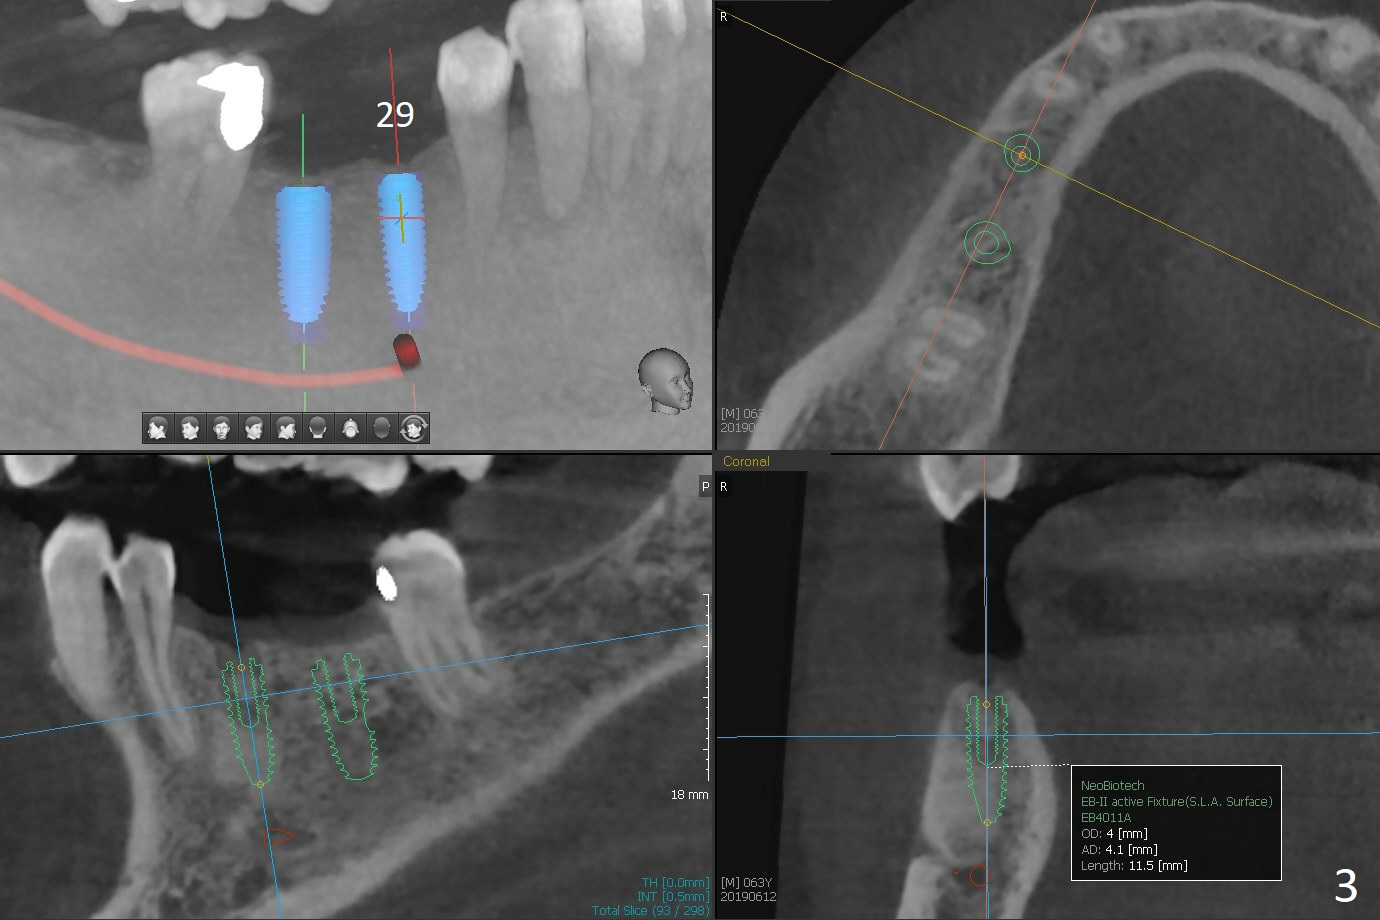

2 mm Bone

A 63-year-old man requests implants to replace a flipper at #29 and 30 (Fig.1). If torque is >25 Ncm for each implant (Fig.2,3 (2 mm bone buccolingually)), abutments will be placed immediately (using planning kit) for splinted provisional. Take photos for the flipper for a good bye party. Composite will be placed at #31 for MO leakage. Remove a small piece of residual root distal to #30 implant with curettage after osteotomy (Fig.4 <).